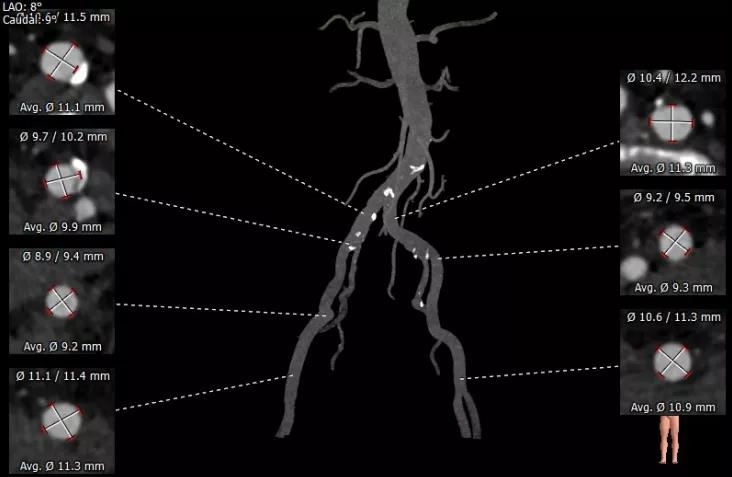

患者男性,67岁,因“劳累后胸闷4月余”入院,术前心脏超声提示主动脉瓣钙化,重度狭窄并轻-中度反流。患者STS评分11.0%,属于常规外科换瓣手术高风险。CT评估结果显示主动脉瓣为Type-1型二叶瓣,瓣叶增厚钙化,瓣环平均直径26.8mm,瓣环面积527.6mm²,面积径25.9mm。左冠脉开口高度10.2mm,右冠脉开口高度11.7mm。术前经详尽影像学重建、评估及病例讨论,测量瓣环直径、分析二叶瓣结构,评估冠脉梗阻风险后,计划植入25# Renatus介入主动脉瓣。

外周血管评估